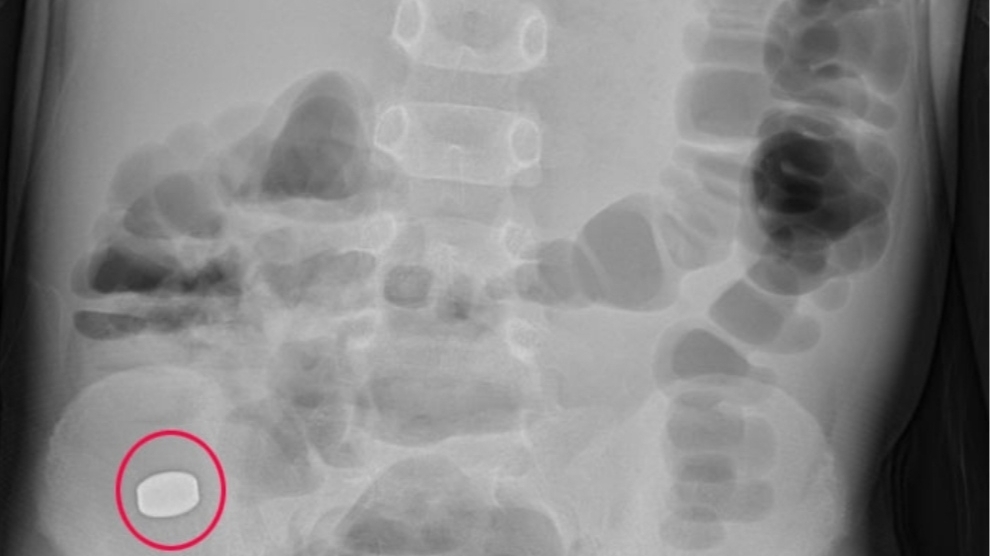

Tương tự, bệnh nhi N.P.V. (nữ, 5 tuổi, trú tại Yên Thành, Nghệ An) có triệu chứng đau bụng vùng thượng vị và quanh rốn. Bệnh nhi được gia đình đưa vào bệnh viện tuyến huyện điều trị. Sau 3 ngày điều trị tại tuyến dưới, bệnh không thuyên giảm, bệnh nhi có triệu chứng đau bụng nhiều hơn kèm nôn ra thức ăn lẫn dịch tiêu hóa 4 - 5 lần/ngày nên được chuyển vào Bệnh viện Sản Nhi Nghệ An.

Khi bệnh nhi làm nội soi tiêu hóa dạ dày - tá tràng, bác sĩ đã phát hiện trong dạ dày có búi tóc cuộn chặt kích thước lớn khoảng 40 x 50 mm, kết dính thức ăn lẫn dịch nhầy có đuôi kéo dài xuống tá tràng. Do khối dị vật kích thước lớn, kết dính, rắn chắc không thể gắp ra ngoài qua đường nội soi tiêu hóa bởi rất phức tạp và không an toàn, các bác sĩ tiến hành phẫu thuật lấy dị vật ra khỏi dạ dày bệnh nhi thành công.